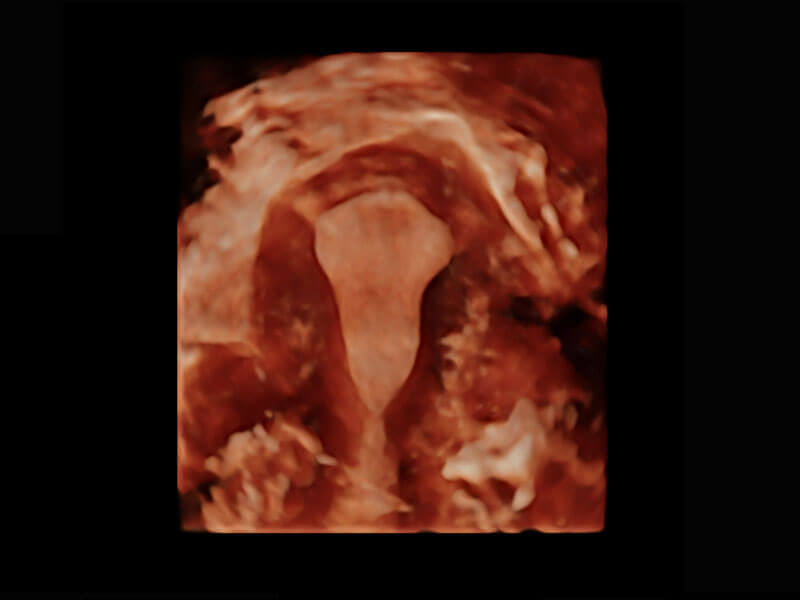

腔内三维-宫内节育器

腔内三维-光影成像

胎心容积成像